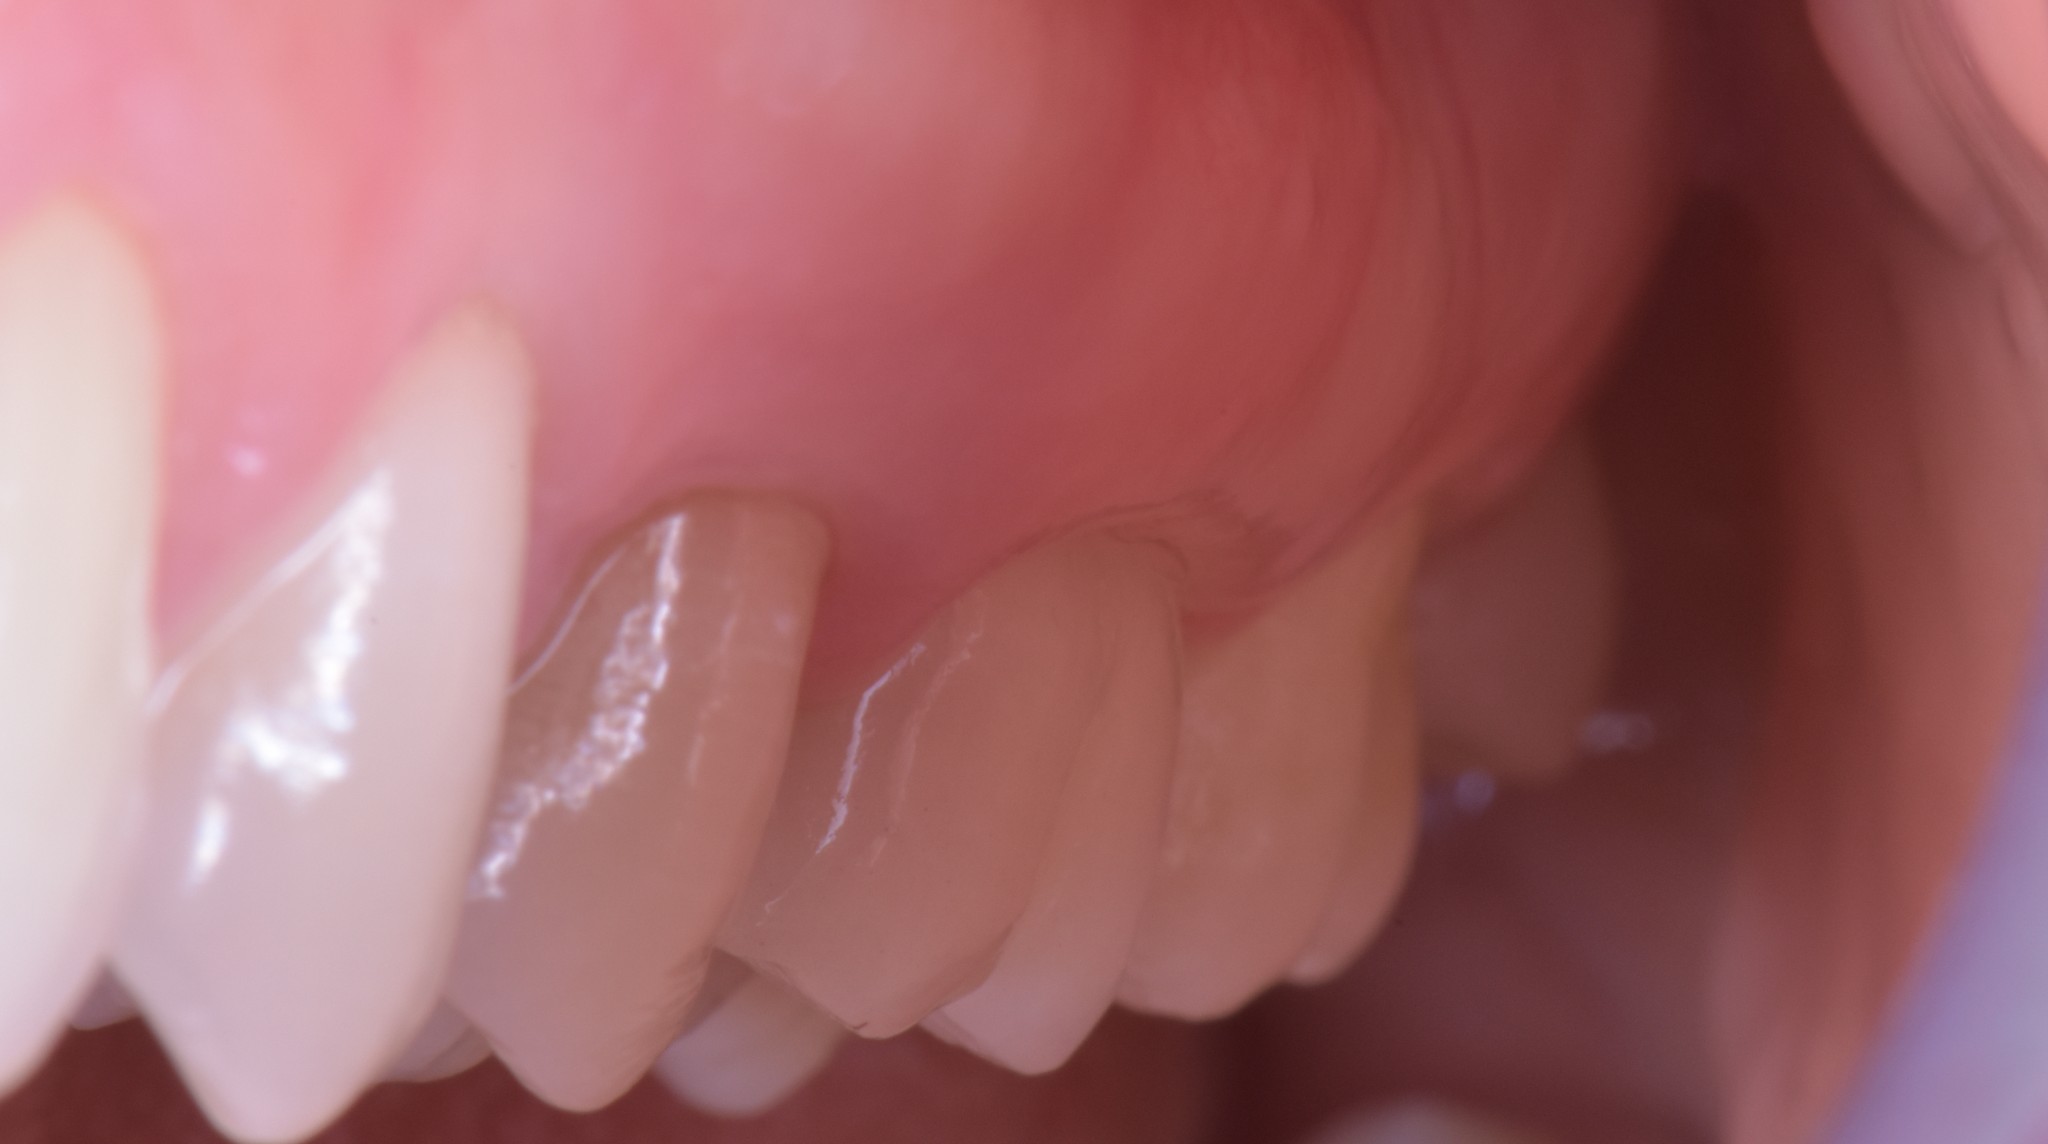

Oggi, dopo circa 5 anni, questa è la foto del “dente” di Valentina. Sono Sicuro che se ti avessi fatto vedere solo questa foto non avresti visto nessun impianto. E ti assicuro che la paziente non ricorda quale sia il dente finto.

In un’infinità di situazioni una corretta gestione dei tessuti molli consente di ottenere ottimi risultati in termini di estetica, confort e mantenibilità.